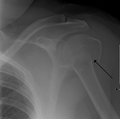

Proximal humerus fracture

A transverse fracture of the humerus shaft

A spiral fracture of the humerus shaft